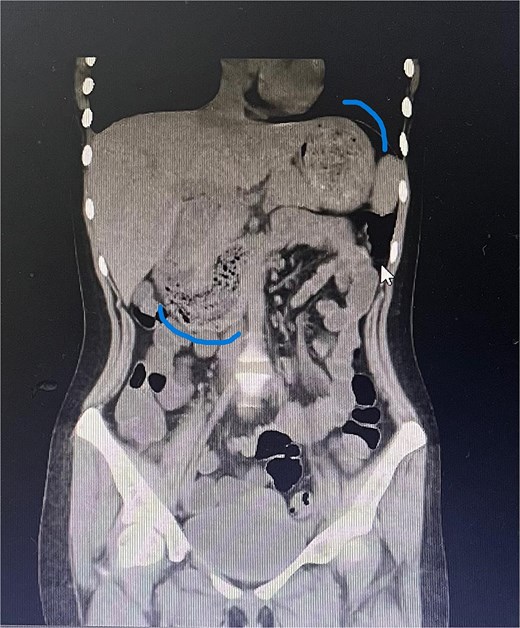

Twelve hours later, she was evaluated by the new emergency surgery team, who found a complete upper obstruction with a foreign body occupying the lower esophagus, the entire stomach, and the entire duodenum (Figs 1–3). A diagnostic laparoscopy (Fig. 10) with gastrotomy was performed (Figs 4 and 5), including foreign body removal (Figs 6 and 7), gastric repair (Fig. 8), and placement of a tubular drain. The findings revealed a large foreign body containing a significant amount of malodorous hair, measuring 30 cm long and 12 cm wide (Fig. 9). Large gauze pads were placed around the stomach to prevent contamination, and the bezoar was removed first through the duodenal area, as this was the area of smallest diameter and least compression. The gastric and esophageal portions were then removed. The foreign body was extracted transumbilically through a small 6 cm incision, protecting the abdominal wall with an isolation device. Gastric repair was performed using a 3–0 continuous suture polydioxanone (PDS) in a single layer. The cavity was irrigated with 3 l of saline solution. The operation was 2 h. Postoperative management included a nasogastric tube on gravity drainage, intravenous piperacillin/tazobactam 4.5 g every 6 h, intravenous tramadol 100 mg every 8 h for analgesia, and intravenous dimenhydrinate 50 mg every 8 h. The patient progressed favorably, with oral intake initiated on postoperative day 4. The tubular drain was removed on day 5 with minimal serous output. Psychiatry discovered that the patient had been diagnosed with trichotillomania in 2014 but refused pharmacological treatment. The patient confirmed that she has suffered from trichophagia since the age of 14. Pharmacological treatment with psychotropic medications and psychological support was initiated. On day 7, the patient was on a soft diet, without a nasogastric tube, with a white blood cell count of 10 740 cells/μl and 0% band neutrophils. Treatment with clomipramine was initiated. She was discharged that day and evaluated 7 days later with no problems.

Sagittal CT image showing the foreign body occupying the gastric cavity and extending into the third and fourth portions of the duodenum.

Sagittal CT image demonstrating the foreign body filling the entire gastric cavity.